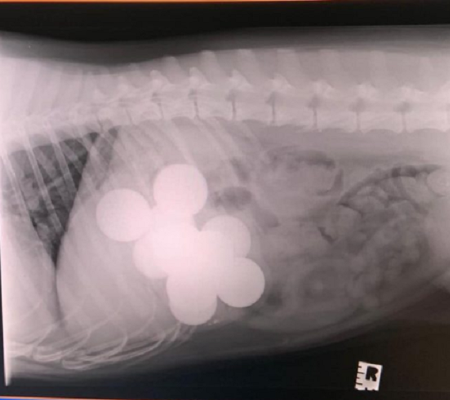

| Foto: MSPCA-Angell, em Massachusetts.

Imagem: Divulgação MSPCA-Angell, em Massachusetts.

O Buldogue, chamado Mortimer, foi atendido pelo MSPCA-Angell, em Massachusetts. De acordo com a assessaoria do hospital, os tutores começaram a preocupar ajuda em abril, quando perceberam que o pet, de 3 anos, ficava enjoado diante dos alimentos. O resultado foi constatado através de um Raio-X. A família só não imaginava que as chupetas dos filhos, que haviam sumido nos últimos meses, fossem parar na barriga do animal.